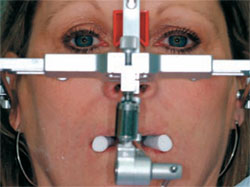

During the preparation appointment, all of the previous restorations were removed and the teeth were reprepared. After the preparations were completed, provisional restorations were made using the putty matrix with Luxatemp® shade B1 (Zenith/DMG, Englewood, NJ), at the new vertical dimension determined by the diagnostic wax-up, trimmed, and set aside (Figure 2A). The provisionals for the central incisors were separated and placed on the teeth to serve as an anterior stop at the proper vertical dimension. The bite registration material (LuxaBite™, Zenith/DMG) was then injected bilaterally and the patient was gently manipulated to closure with the condyles fully seated and the mandibular anterior teeth in light contact with the central incisor provisionals. In addition to this centric relation bite registration, a face-bow transfer, stick bite for horizontal reference (Figure 2B), and a photograph of the stump shade were taken (Figure 2C). After the polyvinyl siloxane impression was made, the teeth were cleaned and the provisional restorations were seated with LuxaFlow™ (Zenith/DMG).

| Figure 2B A face-bow transfer and stick bite were taken for horizontal reference. | Figure 2C Photograph of the stump shade for reference. | |